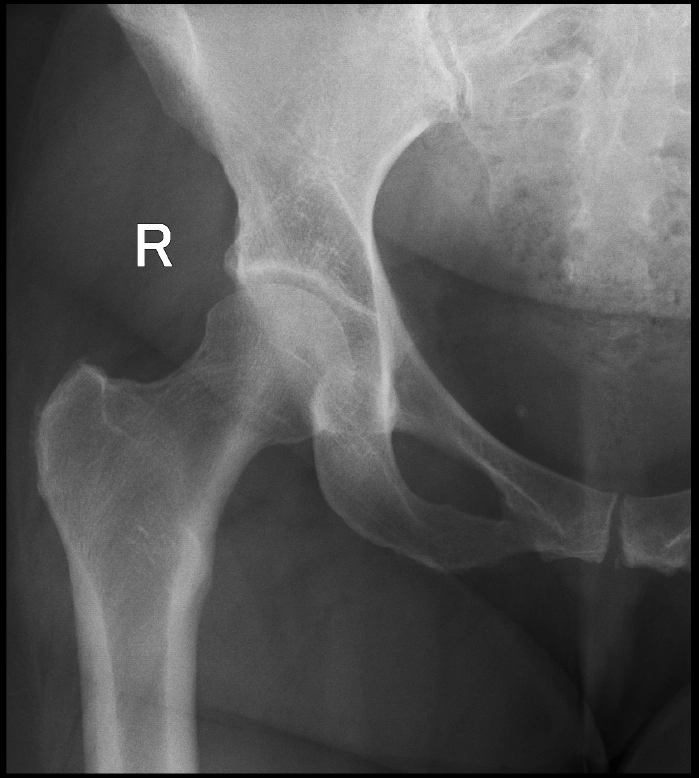

Здоровье суставов: Трохантерит и его влияние на мышцы